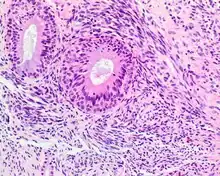

| A high-power view of a hematoxylin- and eosin-stained slide showing respiratory epithelial inclusions within a spindled cell neoplasm showing characteristics of a biphenotypic sinonasal sarcoma | |

- Infiltrative, highly cellular spindled cell neoplasm is poorly circumscribed and unencapsulated. Bone destruction or invasion is common. The cells show medium to long fascicles (nerve fibers), with a herringbone pattern. The cells are remarkably uniform with elongated nuclei. Delicate strands of intercellular collagen without ropy or dense deposition are seen. A very characteristic concurrent surface-type respiratory epithelial proliferation is found from the surface or in small cystic spaces around the cancer cells, often forming glands. The background may have a rich vascularity and usually has a small number of scattered lymphocytes. Extra growths or mitoses are rare, while necrosis, ulceration, and hemorrhage are usually absent.